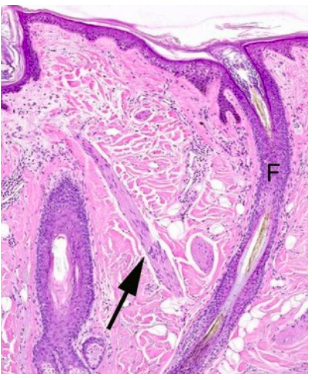

label

what is the arrow pointing to?

arrector pili muscle surrounding a hair follicle